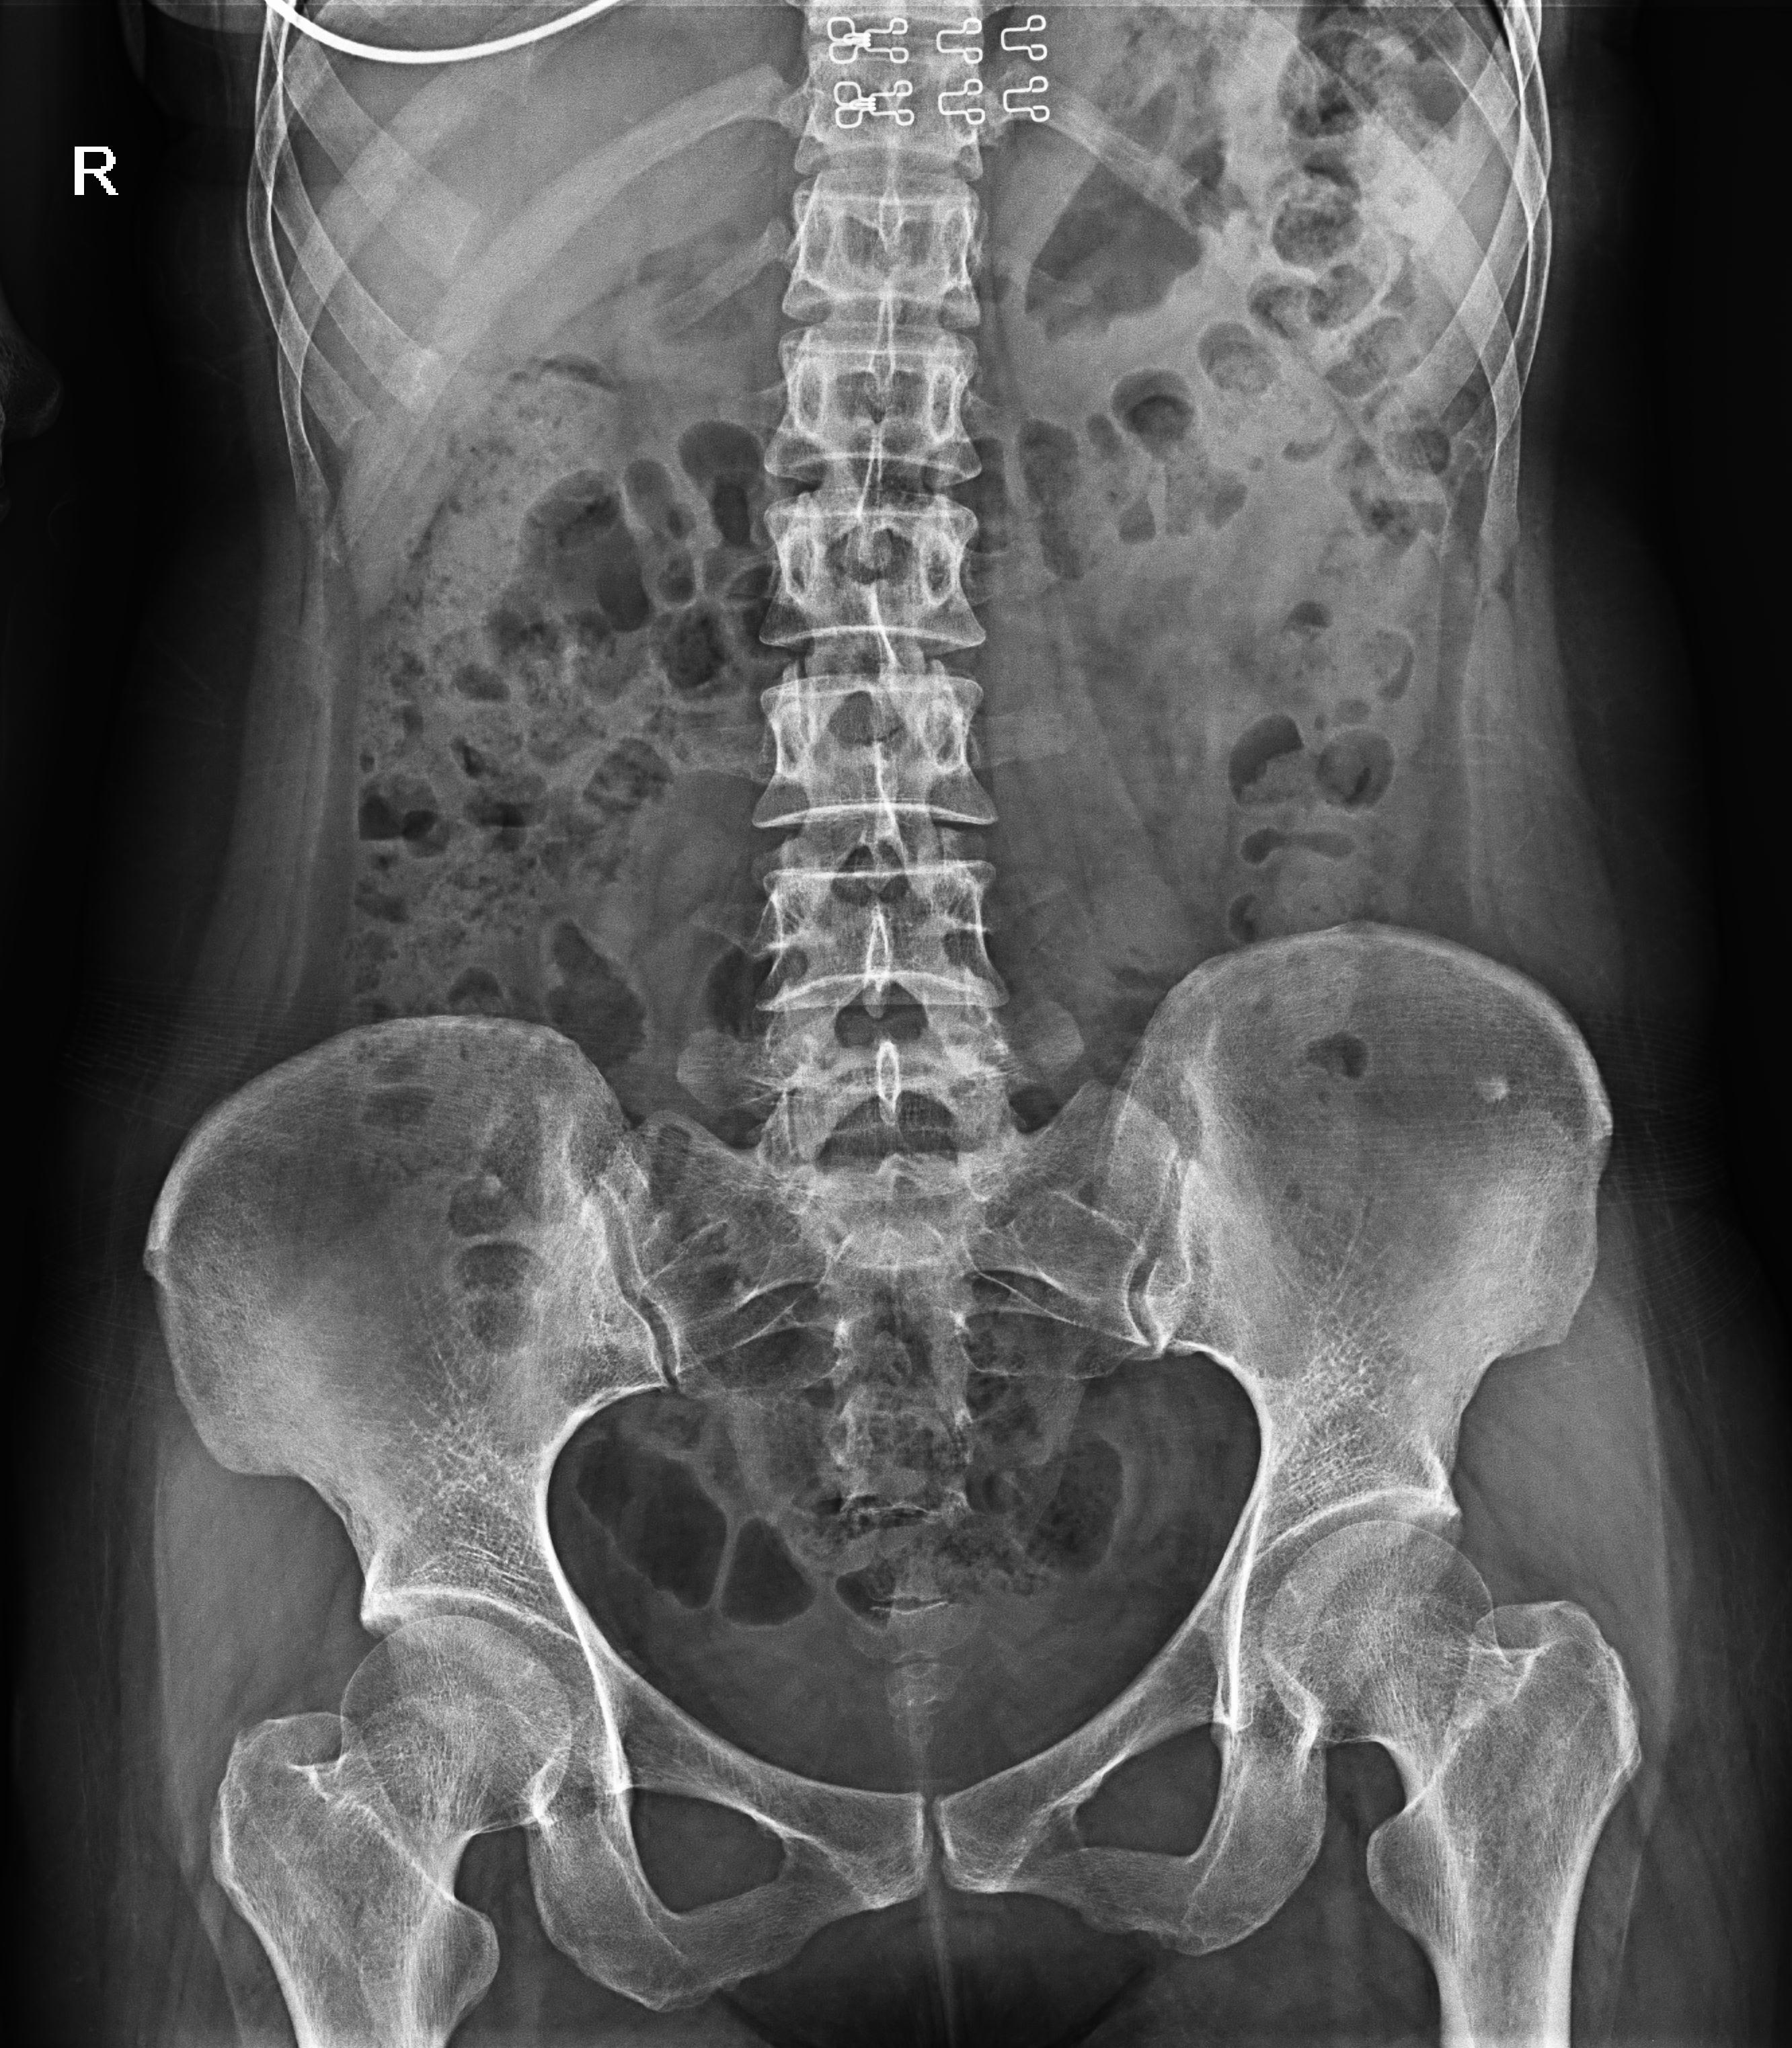

● 獨(dú)特實(shí)用的床面升降功能,有利于DR攝影及行動(dòng)不便的患者上下床;

● 床面可降至與病床平行高度,既方便醫(yī)護(hù)人員平移患者,又避免對(duì)患者的二次傷害;

● 對(duì)于醫(yī)生的近臺(tái)操作也更方便,不同身高的醫(yī)生可根據(jù)需要調(diào)節(jié)床體高度,更利于醫(yī)生開(kāi)展相關(guān)近臺(tái)手術(shù)。